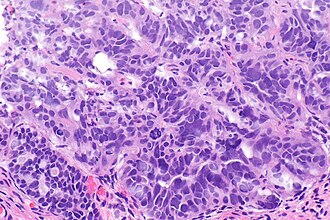

Micrograph of fallopian tube serous carcinoma. H&E stain. | |

Serous carcinoma of the fallopian tube is a serous carcinoma that arise from the Fallopian tube. These are thought to be important in the development of ovarian cancer.[1]